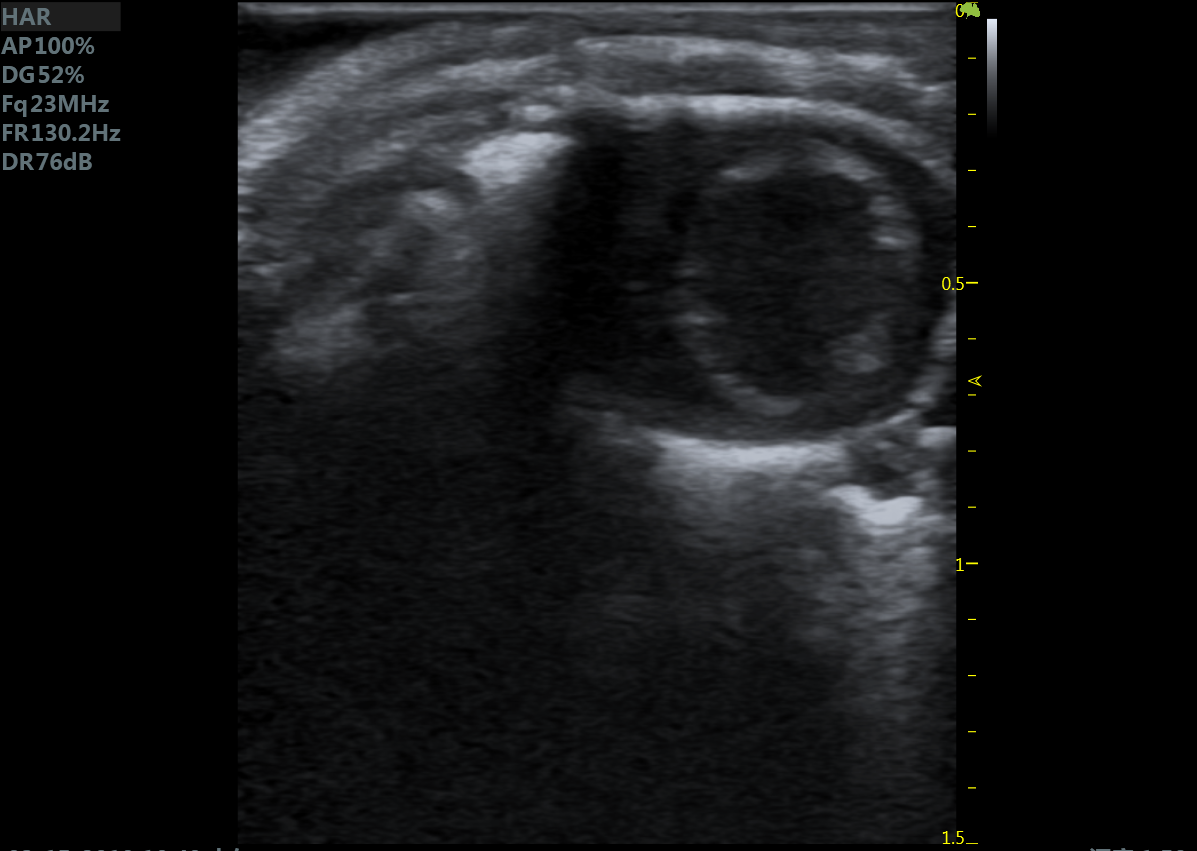

小鼠长轴B型 小鼠短轴B型

大鼠胎鼠心脏血流 大鼠心尖四腔